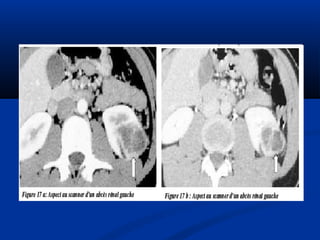

Lao thaänLao thaän

Sieâu aâm:Sieâu aâm:

• **Thaän vaø nieäu quaûn:Thaän vaø nieäu quaûn:

• - Voâi hoaù trong thaän- Voâi hoaù trong thaän

• - Chít heïp = giaõn heä beå- Chít heïp = giaõn heä beå

ñaøiñaøi

• - Hình aûnh coäng: taïo- Hình aûnh coäng: taïo

hang, xoang tuûy…hang, xoang tuûy…

• - Thaän teo nhoû, voâi- Thaän teo nhoû, voâi

hoaùhoaù

• ** Baøng quang :Baøng quang : daøydaøy

vaùchvaùch

Öu theá UIV trong lao nieäuÖu theá UIV trong lao nieäu

SA giuùp ích höôùng daãnSA giuùp ích höôùng daãn

Rein Mastic

Calcifications surrénaliennes

Images d’addition

Hang lao và chít hẹp

Lao niệu quản